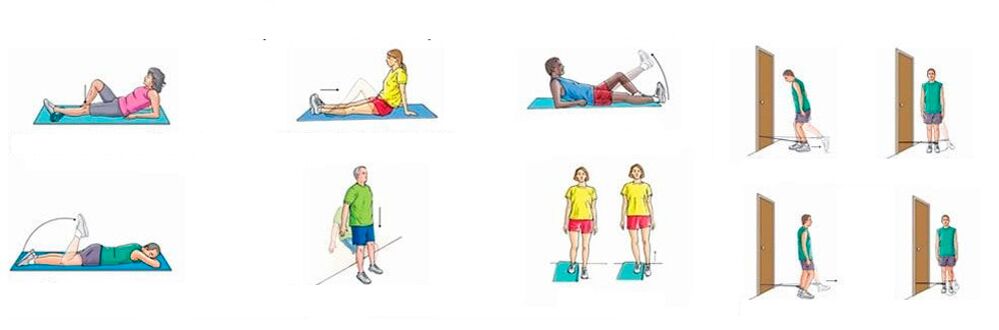

Pour les douleurs chroniques aux articulations du genou, lorsqu'il n'y a pas d'inflammation significative, vous pouvez effectuer des exercices physiques qui renforcent le système musculo-ligamentaire, améliorent la circulation sanguine et le métabolisme. Un entraînement systématique entraîne une diminution progressive de la douleur, malgré le fait que les jambes soient plutôt croustillantes.

Une série approximative d'exercices pour les douleurs au genou :

- Genou fixe. Allongez-vous sur le dos, pliez une jambe au niveau du genou, soulevez-la et maintenez-la dans cet état pendant une minute ; le match retour est immobile à ce moment-là ; redressez et abaissez votre jambe très lentement, reposez-vous pendant 10 secondes et répétez l'exercice avec l'autre jambe ; répétez 10 fois;

- Flexion des jambes doubles avec les genoux près du visage. Allongez-vous sur le dos, pliez vos jambes au niveau des hanches et des genoux, fixez ces derniers près de votre visage et maintenez-le ainsi pendant une minute. Ensuite, redressez et abaissez lentement vos jambes, reposez-vous pendant 10 secondes et répétez ; faites 5 à 6 séries, en augmentant progressivement la charge.

Une douleur aiguë au genou nécessite un état de repos ; toute activité physique et tout entraînement sont contre-indiqués.

En cas de douleur aiguë à l'articulation du genou, accompagnée d'un gonflement et d'une rougeur de la peau, d'une violation de l'état général, de fièvre, vous ne pouvez pas bouger la jambe, elle doit être maintenue au repos. Et seulement après que l'inflammation commence à s'atténuer, vous pouvez passer d'abord à des exercices passifs (effectués par un assistant), puis à des exercices actifs (effectués par le patient lui-même).